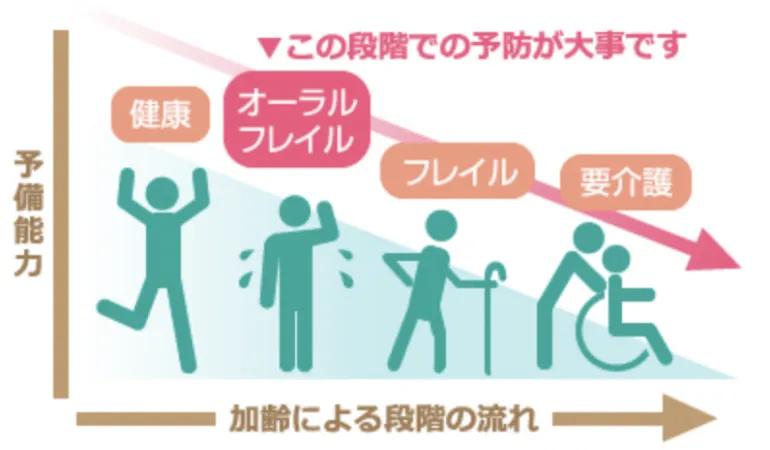

お口の機能を守るためにできる予防

体の機能低下は口腔機能の衰えにも繋がり、咀嚼や飲み込みの問題が発生することがあります。これらの問題を放置すると、日常生活が困難になり、最終的には介護が必要になることも。早期に「オーラルフレイル」を予防することが、健康な生活を維持するための鍵となります。

インプラントは

オーラルフレイルの

段階予防の救世主です

失った歯を補うための治療法として入れ歯やブリッジがありますが、これらは残っている歯に負担をかけるため長期間使用すると歯の消耗を招くことがあります。

インプラント治療により失った歯の部分を復元することで他の歯にかかる負担を軽減し噛み合わせを長期的にしっかりと保つことができます。

「オーラルフレイル」の予防を早期に行うことで健康寿命を延ばすことが可能です。歯に関するお悩みやインプラント治療について、ぜひお気軽にご相談ください。